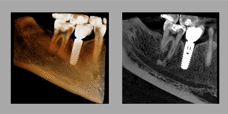

全新X-TREND,震撼将至